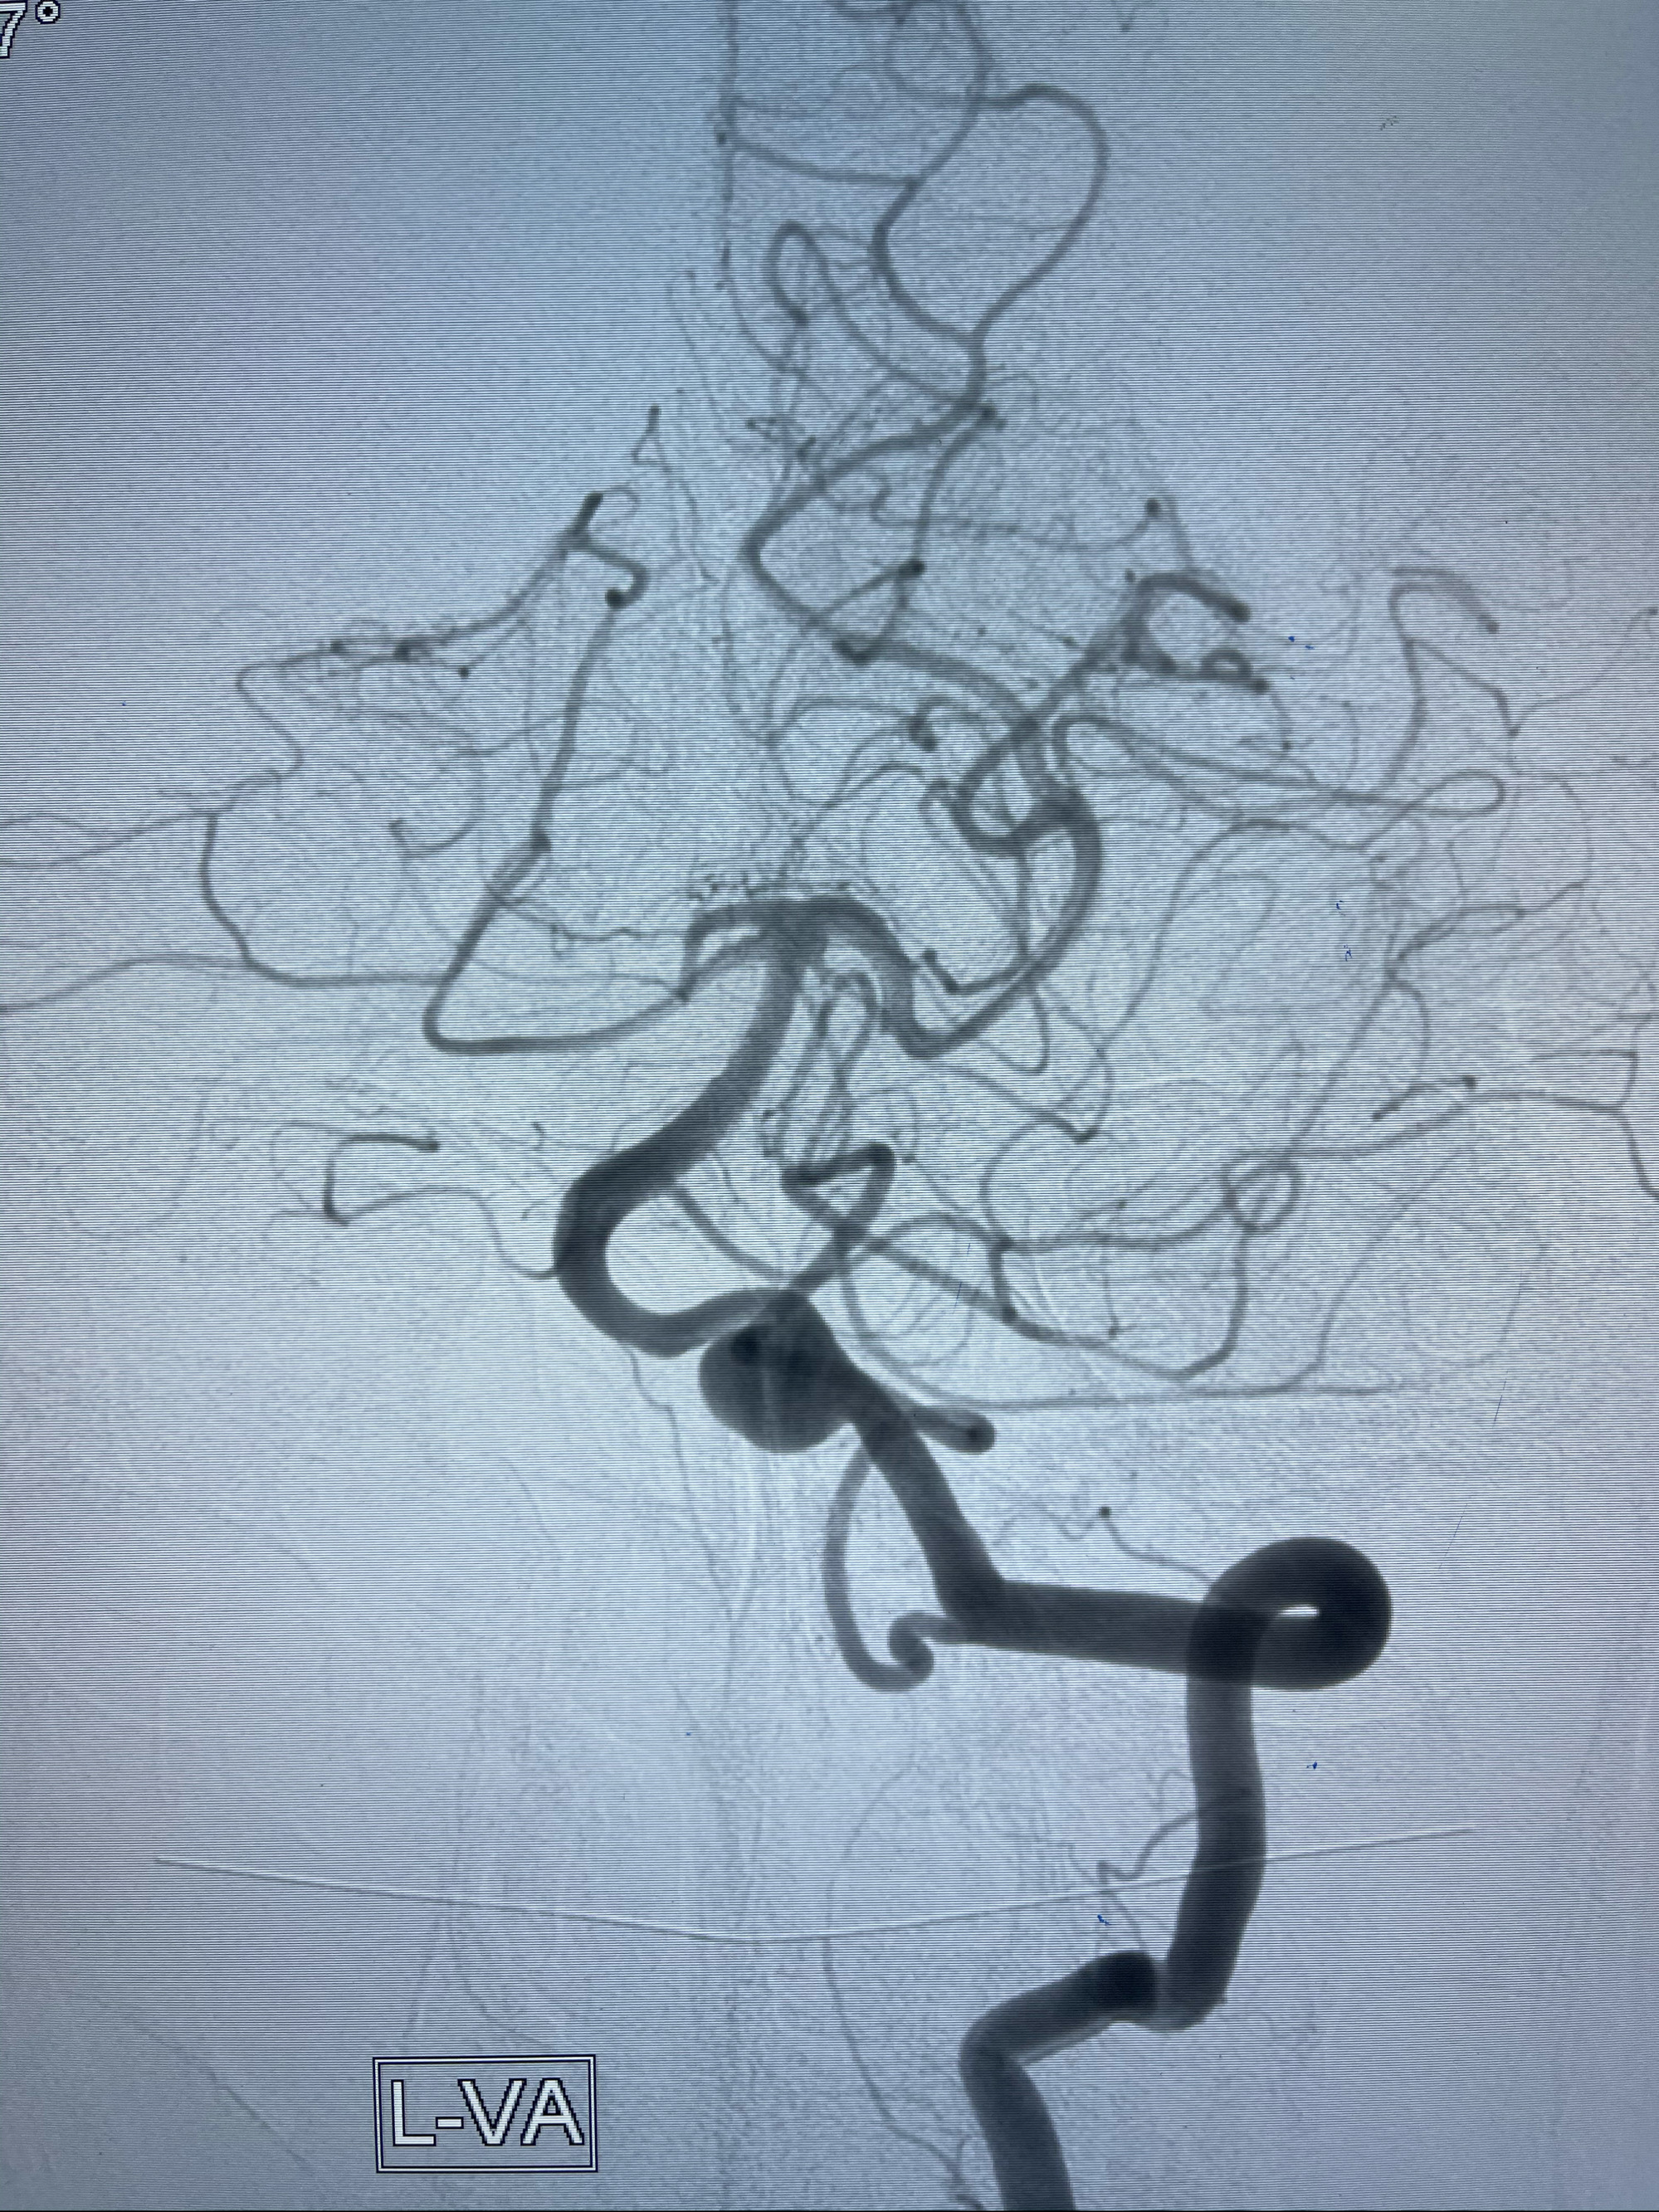

左侧椎动脉V4夹层动脉瘤多支架辅助栓塞:

工作角度造影

即刻造影